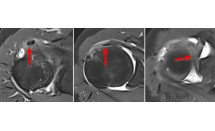

Luxation postérieure de l'épaule